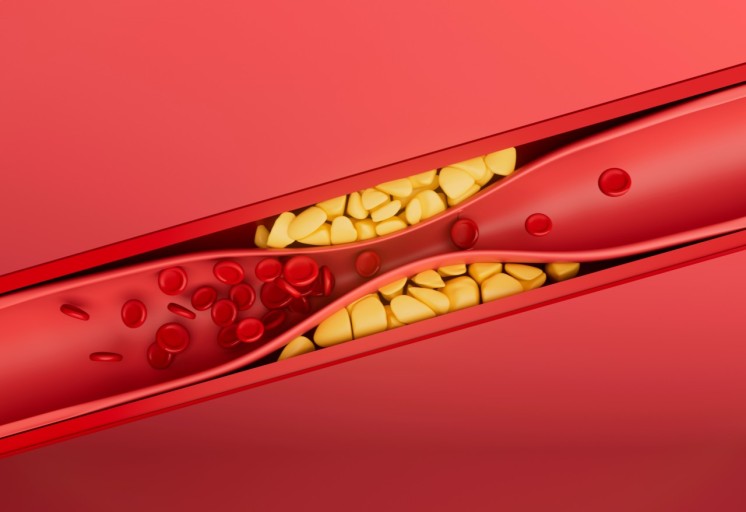

고지혈증 증상 2. 혈액검사에서 LDL 콜레스테롤 수치 상승

눈에 보이지 않지만 가장 정확한 증상입니다.

LDL(나쁜 콜레스테롤) 수치가 높게 나오면

동맥벽에 기름때가 쌓여 혈관이 좁아지고 탄력을 잃게 됩니다.3. 피로감과 무기력증

고지혈증 증상 10. 심근경색 또는 뇌졸중 위험 증가

고지혈증을 방치하면, 혈관 속에 플라크가 쌓이고,

이것이 혈전을 만들어 혈관을 막아버릴 수 있어요.

결과적으로 심근경색, 뇌졸중(뇌경색) 같은 치명적 질환으로 이어질 수 있습니다.